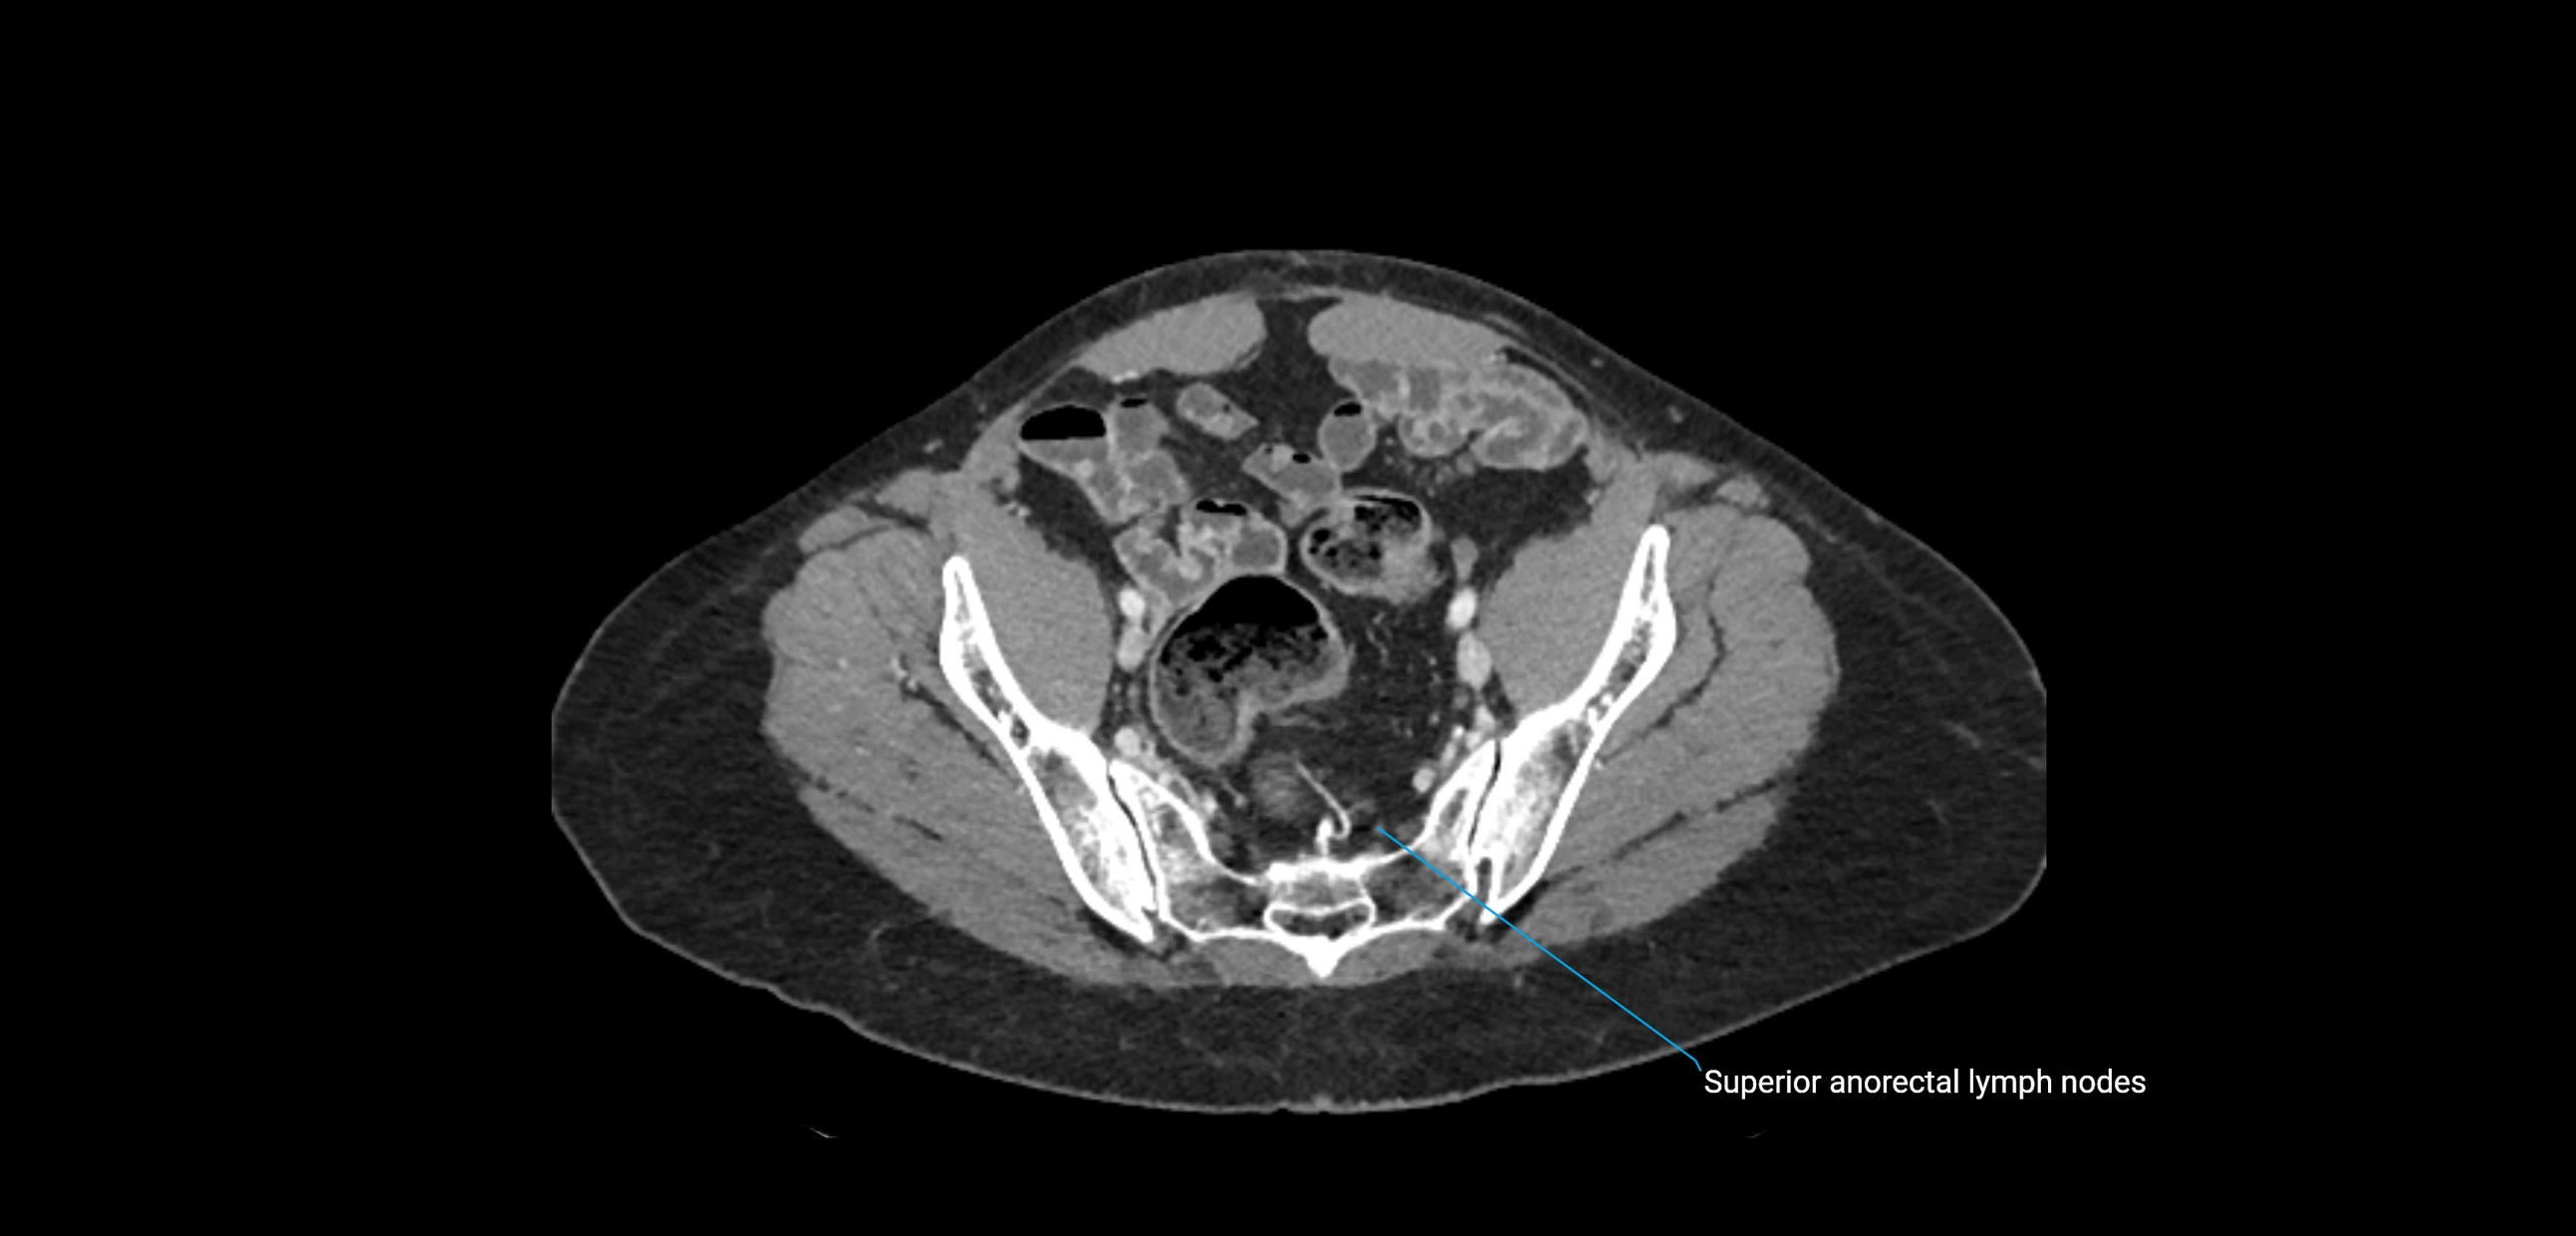

CT Appearance

CT Pre-Contrast:

• Nodes appear as soft-tissue density nodules adjacent to the aorta and IVC

• Calcification may be seen in chronic infections (e.g., tuberculosis)

CT Post-Contrast:

• Normal nodes enhance homogeneously

• Malignant nodes may show heterogeneous enhancement, central necrosis, or conglomerate formation

• Size >1 cm short axis is suspicious, though morphology and distribution are equally important